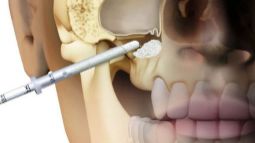

Синус-лифтинг в имплантации зубов

Синус-лифтинг – процедура, предназначенная для наращивания истонченной костной массы. Чаще всего она используется во время подготовки к имплантации на верхней челюсти. В этой части у человека расположены полости, которые сообщаются с носовыми ходами.